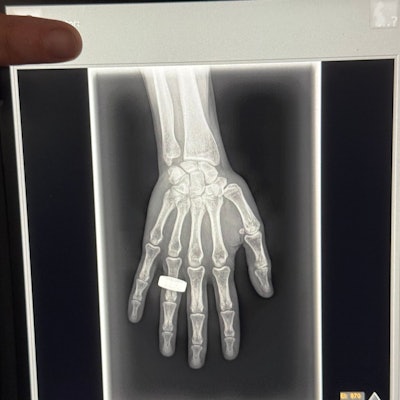

The commander of the Fram2 space mission has posted on social media what may be the first x-ray image taken in space.

In a post on the social media platform X on 1 April, Chun Wu wrote that on the second morning of the flight, the crew woke up, had breakfast, and “took a few x-ray images.”

The post has received over 14.9 million views at the time of writing. The image appears to be a nod to the first x-ray ever taken by Wilhelm Roentgen of his wife Anna Bertha Ludwig's hand on 22 December 1895.

The Fram2 mission launched on 31 March and is expected to be in orbit for at least another day. The crew is conducting more than 20 science experiments, including taking images of each other with an ultraportable x-ray machine.